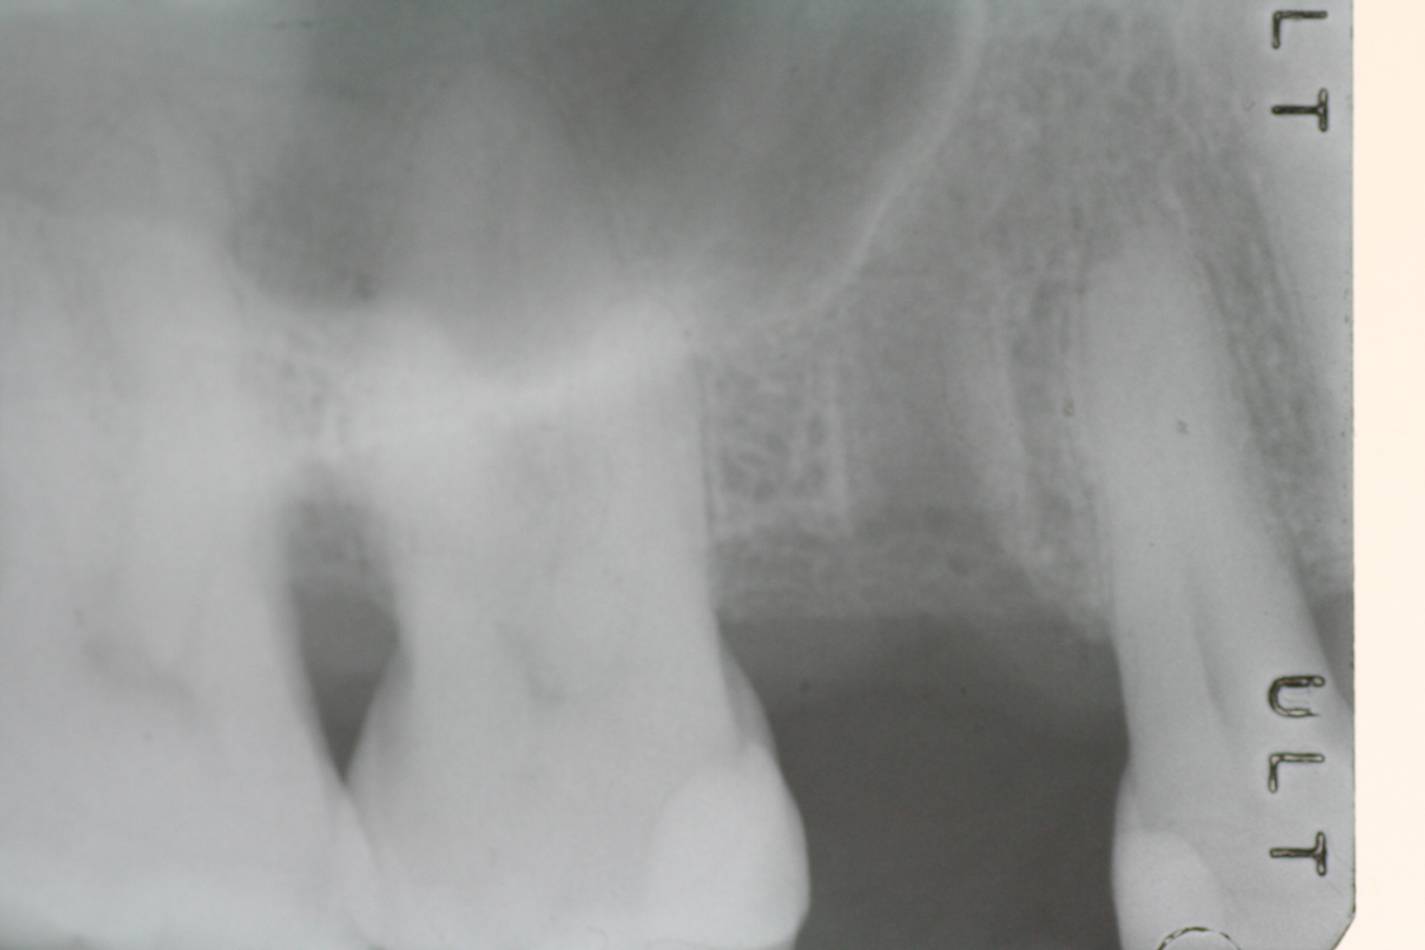

Implantologia e Chirurgia

Si effettua implantologia con impianti STRAUMANN e tecnologia IDI EVOLUTION.